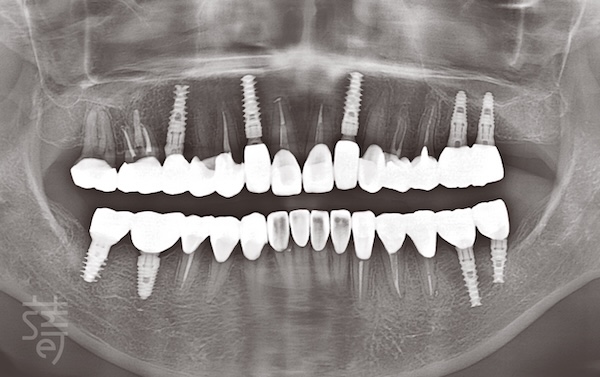

正式修復前,蒔美團隊先為張小姐安排完整咬合分析。不再只是「哪裡壞就補哪」,而是透過多項數位設備,全面評估牙齒的高度、角度、排列與咬合動態。

其中,MODJAW 動態咬合系統是這次重建的關鍵。它能即時模擬說話、咀嚼時下顎的真實運動,精準掌握每顆牙齒在動態中的接觸點與受力狀況。

MODJAW 是目前全球唯一能完整模擬下顎動態的系統,讓治療規劃更貼近真實需求,也讓重建後的假牙、植牙或貼片更穩固、耐用。